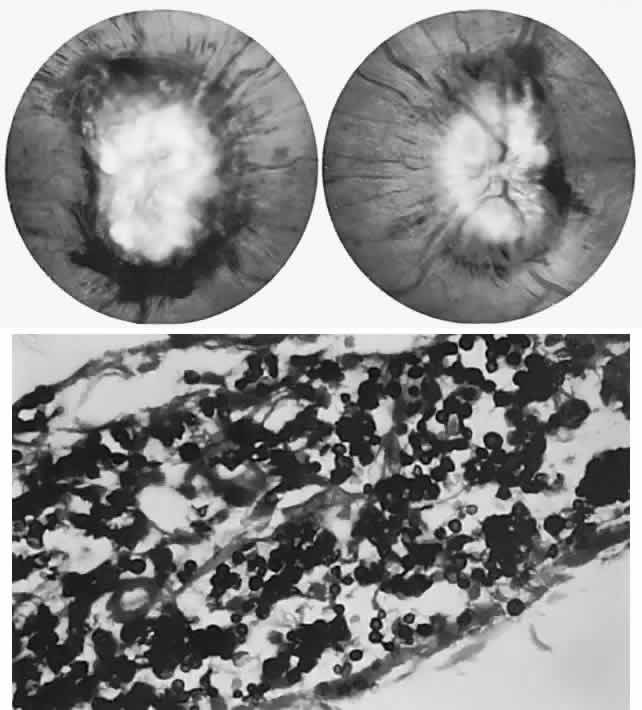

Biochemical assays have considerably clarified the nosologic status of the group of storage diseases previously classified as the “cerebromacular degenerations,” of which Tay-Sachs disease is the eponymous prototype. Although these disorders share a superficial resemblance, showing a progressive neurodegenerative course with variable fundus findings, they are now best classified by abnormal storage products (e.g., sphingolipidoses, mucopolysaccharidoses, and mucolipidoses) and lysosomal enzyme deficiencies. Lysosomes contain hydrolytic enzymes that degrade proteins, polysaccharides, and nucleic acids; if undegraded, these materials accumulate in lysosomes and impair cell function. The complex lipids and saccharides indigenous to neural cells produce symptoms and signs related to eye and brain, including corneal clouding, macular “cherry-red spot,” pigment epithelial degenerations, optic atrophy, mental deterioration, seizures, motor incoordination, myoclonus, and death.

The ganglion cell layer of the retina is a principal site of abnormal accumulation of anomalous storage products, such that ophthalmoscopic changes are observable either in the form of retinal “graying” or the well-known cherry-red spot. The ganglion cell layer densely surrounds the thin fovea, which transmits the normal red color of underlying choroid (Fig. 4). The storage disorders with cherry-red spot or macular graying are listed in Table 2.27

Fig. 4. “Cherry-red spot” of advanced Tay-Sachs disease (gangliosidosis). Note the central foveal window surrounded by a ring of densely opaque retinal ganglion cell layer; also, optic atrophy.